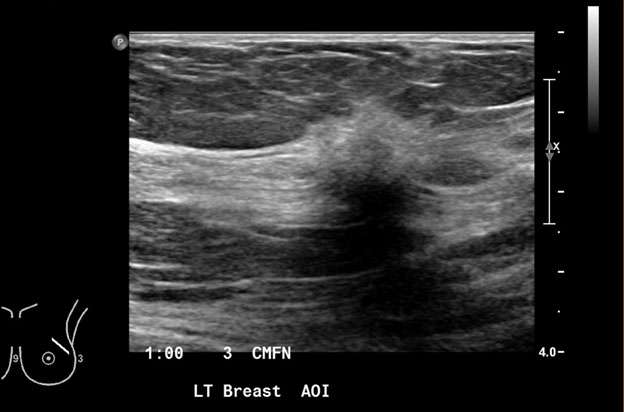

Figure 5: Irregular hypoechoic mass with indistinct margin measuring 1.2 x 1.4 x 1.1 cm in the left breast at 1 o'clock, 3 cm from the nipple was visualized with ultrasound, biopsy was recommended. BI-RADS Category: 4C suspicious finding. Pathology confirmed invasive ductal carcinoma with focal lobular features, grade 2.